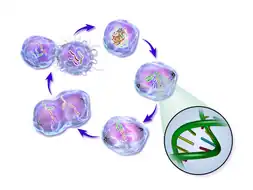

Life cycle of a cancer cell

Life cycle of a cancer cell

Cancer cells are created when the genes responsible for regulating cell division are damaged. Carcinogenesis is caused by mutation and epimutation of the genetic material of normal cells, which upsets the normal balance between proliferation and cell death. This results in uncontrolled cell division in the body. The uncontrolled and often rapid proliferation of cells can lead to benign or malignant tumours (cancer). Benign tumors do not spread to other parts of the body or invade other tissues. Malignant tumors can invade other organs, spread to distant locations (metastasis) and become life-threatening.

More than one mutation is necessary for carcinogenesis. In fact, a series of several mutations to certain classes of genes is usually required before a normal cell will transform into a cancer cell.[5]

Damage to DNA can be caused by exposure to radiation, chemicals, and other environmental sources, but mutations also accumulate naturally over time through uncorrected errors in DNA transcription, making age another risk factor. Oncoviruses can cause certain types of cancer, and genetics are also known to play a role.[6]